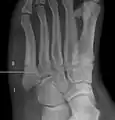

كسر جونز (بالإنجليزية: Jones fracture) هو كسر يصيب قاعدة المشطية الخامسة للقدم، وهي المشطية الواقعة عند قاعدة إصبع القدم الأصغر. ويشكو المصاب بهذا الكسر من ألم وتورم بهذه المنطقة مع صعوبة في المشي.

يظهر الكسر أقصى يمين الأشعة في قاعدة المشطية الخامسة